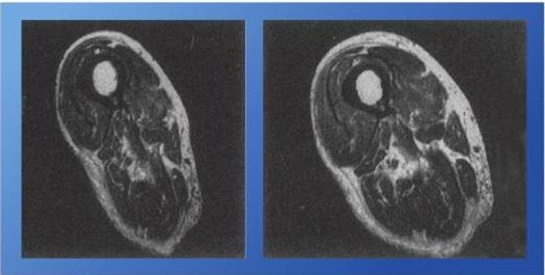

Bildet under viser MR bilde av lårmuskelen til en mann på 92 år (til venstre), bildet til høyre er den samme mannens lårmuskel etter to år med målrettet styrketrening. Den 94 år gamle muskelen har 48% mer muskelmasse enn den på 92 år! (McArdle, Katch og Katch 2010)